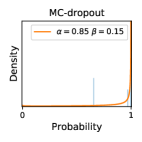

To model how different classifiers will respond to a given input , we assume that the prediction from classifier is sampled from a beta distribution that is characterized by two parameters by and . We further assume that is fixed to the same constant value for all ’s. Under this assumption, each input can be described by ( can be calculated since is fixed), easing further analysis. The Severity Level (SL) of the case represented by image can be characterized by the parameter . The larger the value of , the more severe the case of is. When and are close, the case is ambiguous as the distribution shifts towards being symmetric (i.e. signifying much disagreement among classifiers) rather than being one-sided (i.e. consensus among classifiers that is negative or positive). We provide a set of examples in Figure 2 and also Figure S.8 in the supplementary materials showing how the beta distribution can be used to capture diverse predictions given by an ensemble learner.

We conducted a case study on diagnosing diabetic retinopathy with ensembles of DL models. For benchmarking the performance of our ensemble-based solutions under the scheme described in Sec.3.3, we used two popular collections of diabetic retinopathy image data, the Kaggle Diabetic Retinopathy dataset [22] (hereafter referred to as “Kaggle-DR”) and the Messidor-2 dataset [23], each respectively consisting of and high resolution images. Diabetic retinopathy is graded into five SLs, as displayed in Figure 2. Following the problem setup used in previous papers [24], we trained models to distinguish the referable (SL2-4) cases from the non-referable ones (SL0 & SL1) (see Section B.1 for more detailed descriptions). We also tested our trained ensemble models on two o.o.d. image datasets (ImageNet [25] and CIFAR-10 [26]) to examine their capabilities of identifying o.o.d. inputs (see Section B in the supplementary materials).

In contrast, the MC-dropout method showed the worst overall performance among the three, as it can be seen from the high ratios of SL0 examples among the uncertain negatives in Figure 4. The histograms in Figure 2 provides another perspective to look into the phenomenon, where a decent proportion of MC-dropout model’s predictions on SL0 inputs entailed low confidence (far from 0 or 1), which from another angle explained why MC-dropout was less specific in terms of lower FNP; many no-DR inputs (i.e. SL0) were erroneously assigned high uncertainty by MC-dropout models.

It is still an open question why the evaluated MC-dropout networks signaled relatively high uncertainty on SL0 & SL3 & SL4 data that are less likely to be ambiguous. We conjecture that much of the “uncertainty” indicated by disagreement among test-time dropout samples actually reflects the stochastic nature of dropout networks rather than the real decision uncertainty associated with the data. It is worth noting that the MC-dropout model we evaluated was not weak per se; they all achieved above Area Under Curve (AUC) scores on test sets. The weakness of individual test-time samples (which explains their low-confidence predictions on SL0 & SL3 & SL4) might have been hidden when they are aggregated into an ensemble—a well-known advantage of ensemble learning. Our results suggested that the uncertainty information given by implicit ensemble methods such as MC-dropout and TTA might not be as reliable as that from explicit ensemble approaches (e.g., stacking ensembles). Similar findings on MC-dropout can be found in some previous papers [1].